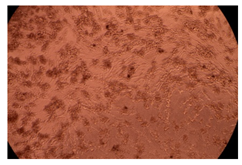

2.4. In Vitro Cytotoxicity Analysis

| Control |  |  | |

| Cop B | 10 µg/mL |  |  |

| 50 µg/mL |  |  | |

| 100 µg/mL |  |  | |

| Cop B/IMC = 10/1 (wt/wt) | 10 µg/mL |  |  |

| 50 µg/mL |  |  | |

| 100 µg/mL |  |  | |

| Cop B/Dorzolamide = 10/1 (wt/wt) | 10 µg/mL |  |  |

| 50 µg/mL |  |  | |

| 100 µg/mL |  |  | |